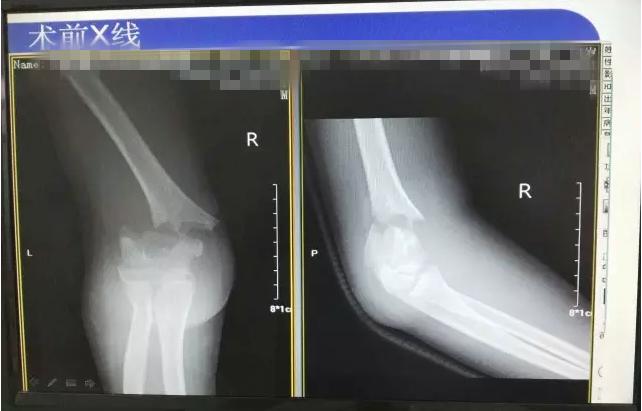

病案二:患儿谭XX,男,14岁,摔伤后右肘关节疼痛伴活动受限5小时入院。

诊断:Gartland III型骨折